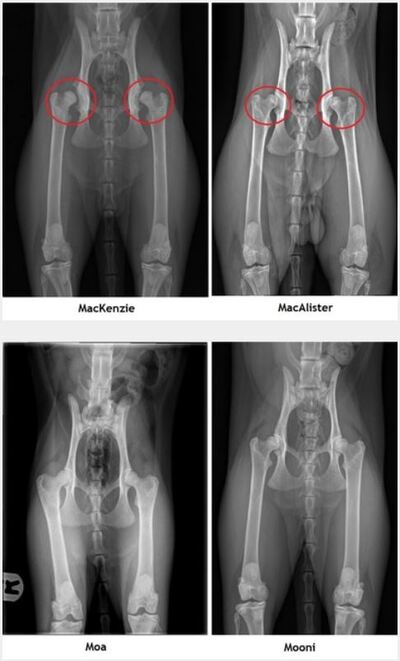

Toen bij MacKenzie echter HD graad 3 werd vastgesteld, hebben we alle andere eigenaren geïnfomeerd en zijn alle nestgenoten op onze kosten getest. MacAlister bleek als enige ook HD te hebben: graad 2 beiderzijds. Hierdoor vielen onze plannen voor een nestje met hem in het water.

Met zo’n 10 maanden oud hadden Hanne en Glenn door dat er iets niet klopte met Snow. Als ze hem oppakten hoorden ze een schrapend geluid. Hij leek verder geen pijn te hebben, at goed en speelde volop. Uit de röntgenfoto’s bleek dat hij HD graad 3 had aan beide zijden.